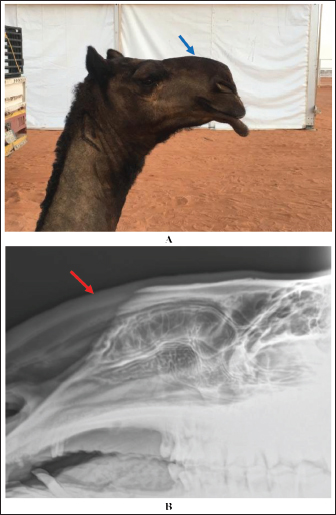

Extension and stretching of the lips in camels due to daily massage of the lips and sometimes binding with a rubber band resulted in blood congestion and lip enlargement (Fig. 7). Radiographic evaluation of filler materials in the perinasal region showed swelling of the soft tissues to the extent of variable degrees owing to the injected fillers; the injected substances appeared gray and had a soft tissue density (Fig. 8). In the injected lips, the injected filler was hypoechoic, and the scanning manner of the injected lips appeared heterogeneous (Fig. 9). In the perinasal area, the filler material appeared as either hypoechogenic or anechoic spots (Fig. 10). In infrared thermography (IRT), stretched lips appeared lighter and more heterogeneous than the darker and homogenous lips of healthy camels. In addition, the injected lip sites appeared darker than the surrounding tissue as their temperature was relatively higher when compared with healthy non-injected lip tissue (Fig. 11). Figure 12 shows a camel with enlargement of the lips due to filler injection, while Figure 13 shows enlargement of the soft palate or dulla and clitoris due to testosterone hormonal injection.

Fig. 8. Enlargement of the perinasal area in a female camel due to injection of filler material (blue arrow) (A). Image (B) shows a lateral radiographic view of the same camel, showing the gray-colored injected filler material in the perinasal region (red arrow).

Radiography is also valuable for determining the injected filler materials in the perinasal region. Radiographic evaluation revealed swelling of the soft tissues to different extents owing to injected fillers; the injected substances appeared grayish with a variable soft tissue density. This finding was not correlated with those reported by Kwon et al. (2018), who found the radiopaque density of an unknown filler material in three cases, and Valiyaparambil et al. (2009) who reported a case of an unusual soft tissue radiopacity-radiographic appearance of dermal filler. The reason for the differences detected in tissue density may be due to the various types of injected fillers, whereas the most popular injected filler material in camels is hyaluronic acid (Tharwat and Al-Hawas, 2021). Our findings clearly demonstrate the usefulness of radiography as a diagnostic imaging technique for the precise detection of injected cosmetic fillers in the perinasal area and as a tool for detecting their expansion in the soft tissues. These findings agree well with recently reported findings in humans (Kroumpouzos et al., 2023) and camels (Tharwat et al., 2024b). The use of radiography in this study has some disadvantages. These drawbacks include not using the X-ray machine near the camels, as radiography can only be used in closed, protected rooms lined with lead. Therefore, it was necessary to move the suspected camel to safe places where the X-ray machine could be used, which would consequently waste time.